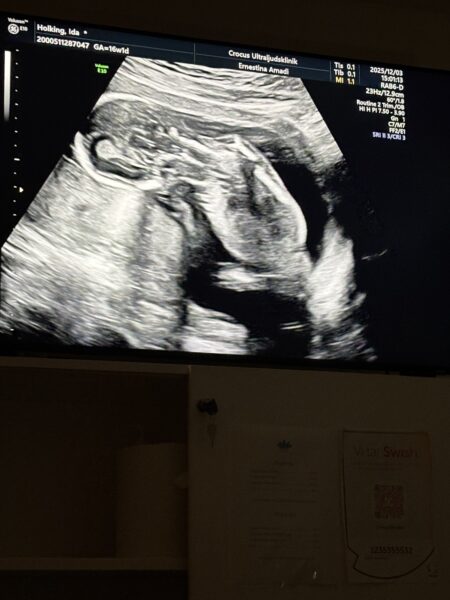

Idag hade Ida ett ultraljud för köns-bestämning. Ida väntar en liten flicka 🩷🩷🩷

Idag gick hon också in i vecka 17….. och dagens barnmorska gjorde en ny bedömning av beräknad förlossning: 16 maj 2026 🙈

Vi fick också höra hjärtljud för första gången 🩷